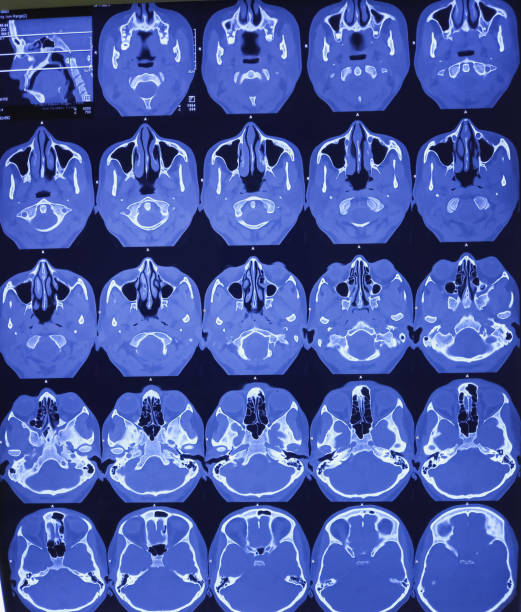

When symptoms persist, seeking medical evaluation from an Ear, Nose, and Throat (ENT) specialist becomes imperative. Diagnostic procedures may include nasal endoscopy, imaging studies, and allergy testing. These methods allow for a precise diagnosis, laying the foundation for an effective treatment plan.